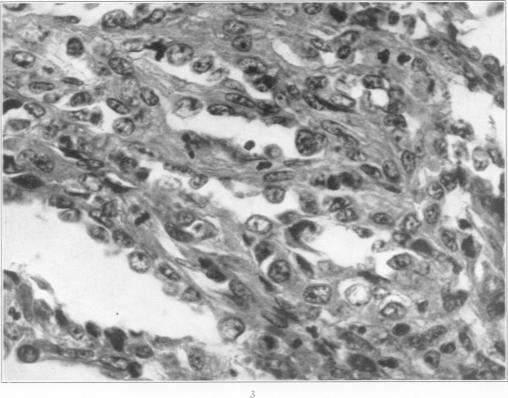

A Malignant Hemangioma of the Lung with Multiple Metastases.

Am J Pathol. 1935 Mar;11(2):343-352.3.